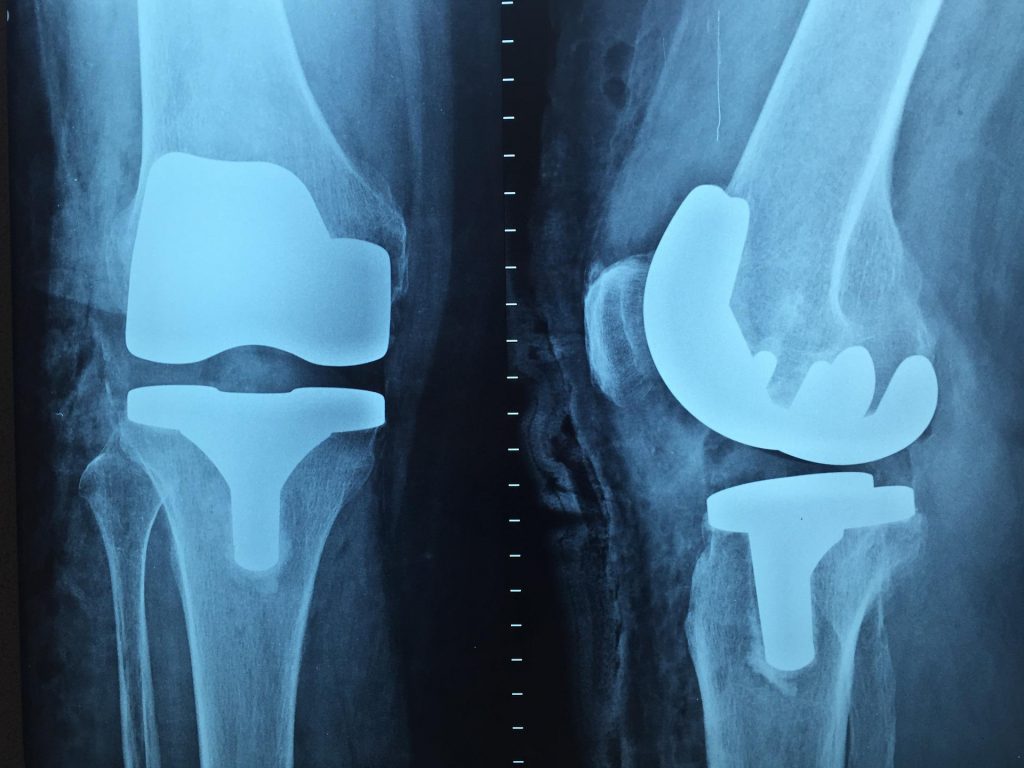

In der rechten Abbildung ist eine Kniegelenks-Totalendoprothese (KTEP) eines rechten Kniegelenks im Röntgenbild zu sehen. Aufgrund der höheren Molaren Masse der verbauten Titan-Nickel-Legierung wird Röntgenstrahlung stark absorbiert und es kommt zur deutlich hellen Abbildung im Röntgen.